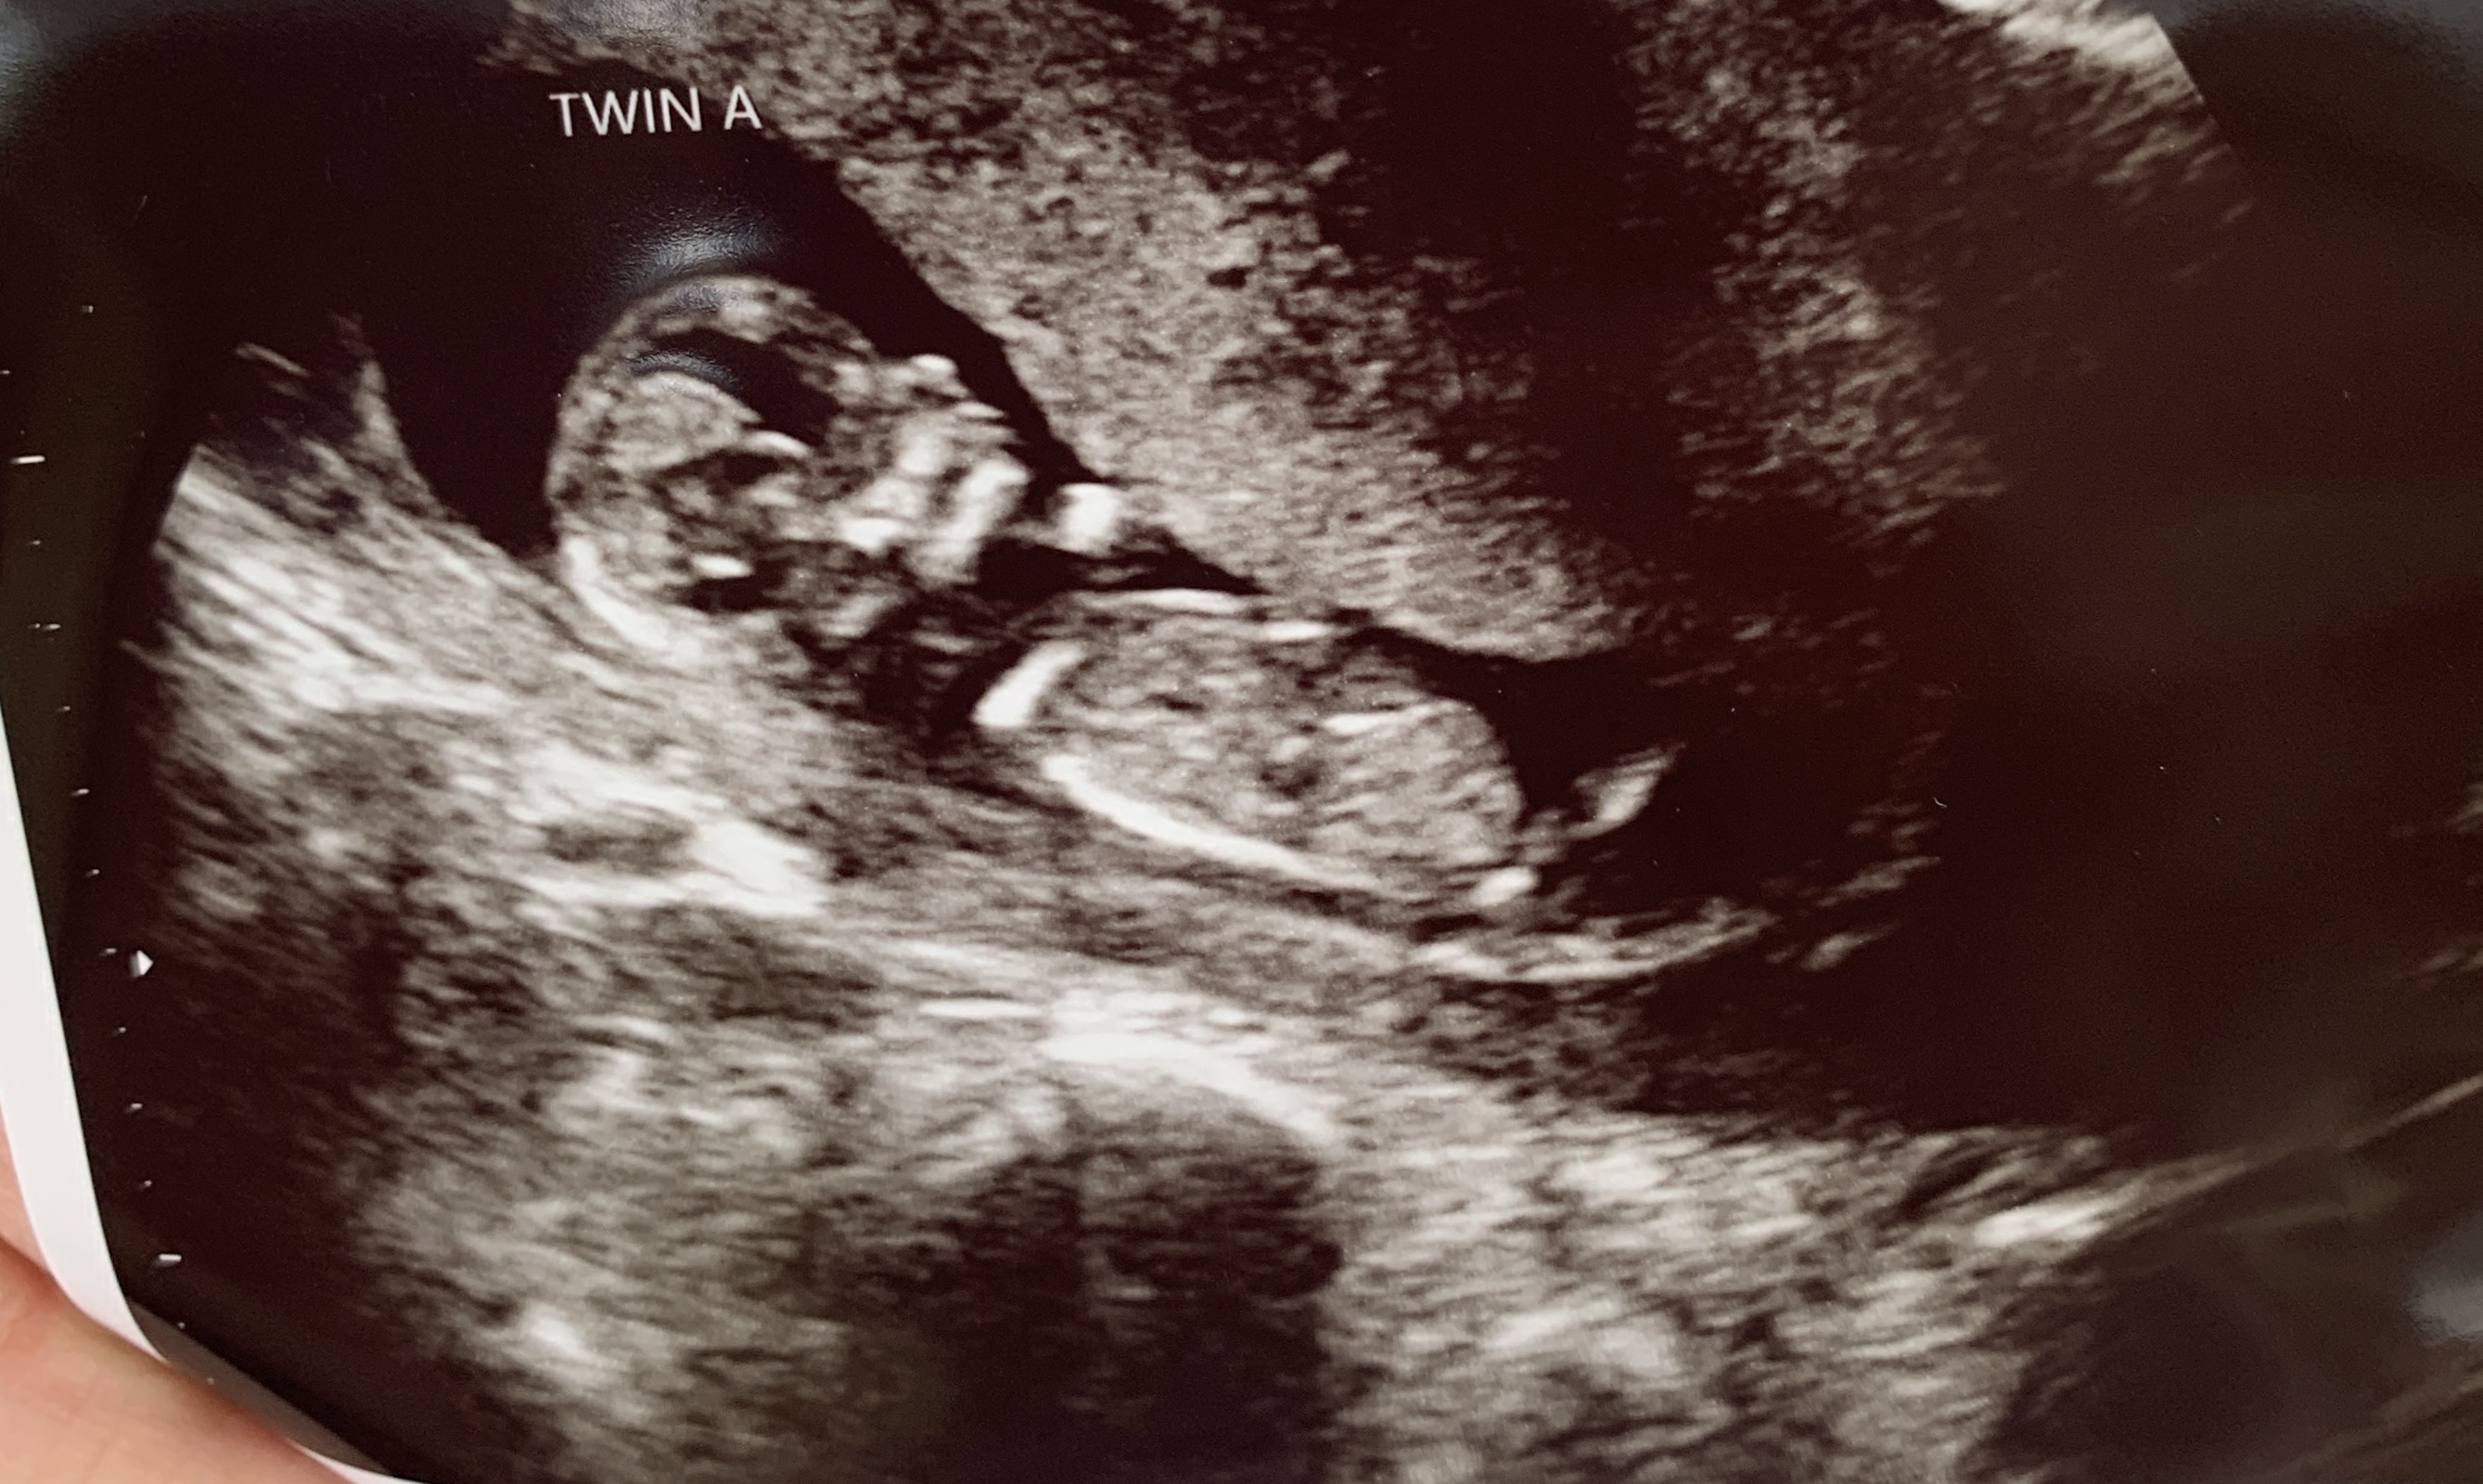

This is a twin transvaginal ultrasound at 7w3d